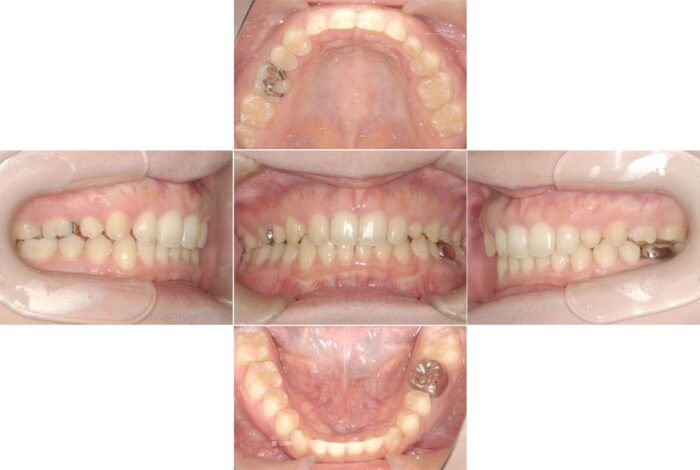

マウスピースと部分的にワイヤー矯正を併用した症例

部分的にワイヤー矯正をつけてマウスピースとワイヤー矯正を併用して治療を進めることもあります。

前歯のすきっ歯の改善と目立たない矯正装置を希望され、マウスピース矯正装置(インビザライン)で治療を始めました。ところが、治療開始5ヶ月を過ぎた頃から、大学生になり環境の変化で、通院間隔が9ヶ月間も空いてしまいました。

そのため、マウスピースが合わなくなってしまい、ワイヤー矯正へ変更の提案をしましたが、目立つ装置は避けたいということで奥歯だけワイヤー矯正をつけて補正することになりました。

7ヶ月間、装置を併用した治療を行い、その後マウスピースのみで細かい微調整とかみ合わせの調整を行いました。通院間隔が空いてしまったこと以外は問題なく治療が進み、すきっ歯が改善されました。

【症例詳細】

- 主訴:すきっ歯が気になる

- 診断名:空隙歯列・過蓋咬合

- 初診時年齢:17歳・女性

- 使用装置:マウスピース矯正装置(インビザライン)・表側ワイヤー矯正

- 抜歯部位:上顎左右犬歯・上顎左側第二小臼歯(欠損)、上顎右側乳犬歯

- 治療期間:3年6ヵ月

- 費用:865,000円(税込951,500円)

- リスクと副作用:痛み、歯根吸収、歯肉退縮、むし歯、後戻り